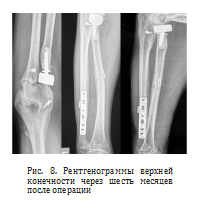

После хирургического вмешательства пациент проходил реабилитацию на протяжении шести месяцев. Контрольные рентгенограммы и компьютерная томография выполнили через полгода с момента операции. На рентгенограммах предплечья отметили срастающийся перелом локтевой кости (рис. 8).

По шкале Мейо, описывающей функцию запястья, результат оценен как «хороший» [19]. Отмечено увеличение объема движений в левой руке: сгибание предплечья — 160°, разгибание предплечья — 170°, пронация — 85°, супинация — 75°, разгибание кисти — 65°, сгибание кисти — 45° (рис. 9). Пациент полностью адаптировался к бытовой жизни и вернулся к профессиональной деятельности мастера тентового производства.